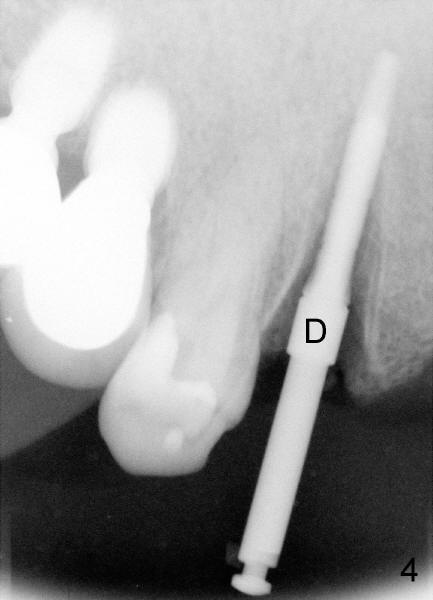

Immediately after atraumatic extraction of #6 residual root, the socket is irrigated with normal saline and Chlorhexidine. There is no granulation tissue in the apical area. The root stump is 6 mm mesiodistally and 8.5 mm labiopalatally. Tatum 2 mm pilot drill is used with copious irrigation to penetrate the palatal plate of the socket (as shown by arrow in Fig.2) at the depth of 20 mm from gingival margin. Bicon reamers (cylindrical, from 2.5 mm to 4.0 mm in a sequential order) are used (with 400:1 reduction) for osteotomy without irrigation. Autogenous bone graft is collected to fill the gap between implant and socket. Fig.4 shows 3.0 mm reamer in place (20 mm from the gingival margin). Finally Tatum tapered implant 6x20 mm is torqued in with primary stability (Fig.5: I). There is no gap between the implant and the socket except palatally, where the bone graft is inserted. Two release incisions are placed palatally. The flap is raised. The periosteum is scored at the base. The palatal flap is advanced labially to close the palatal gap with 4-0 chromic gut suture.